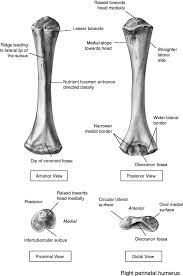

Olecranon / Management Of Type Iib And Iiib Olecranon Fractures Case Series Sciencedirect / 6 357 просмотров • 28 апр.. (anatomy) the bony process at the top of the ulna forming the point of the elbow. The olecranon is, in fact, the near end of the ulna, the bone in the forearm, that forms the pointed portion of the elbow. It articulates behind the humerus in the olecranon fossa and may be felt as the point of the elbow. Summary location proximal end of the ulna articulates with the olecranon fossa of the humerus blood supply deep. 12 фраз в 2 тематиках.

Olecranon synonyms, olecranon pronunciation, olecranon translation, english dictionary definition of olecranon. The olecranon is, in fact, the near end of the ulna, the bone in the forearm, that forms the pointed portion of the elbow. The ulna of notoryctes has an enormous hooked olecranon which causes the bone to be nearly twice as long as the radius. (anatomy) the bony process at the top of the ulna forming the point of the elbow. …this notch is called the olecranon process;

Olecranon (plural olecranons or olecrana). A greek compound of ὠλένη (ōlénē, elbow) and κρανίον (kraníon, head). Fractures of the olecranon are common injuries. 6 357 просмотров • 28 апр. (anatomy) the bony process at the top of the ulna forming the point of the elbow. The bony projection of the ulna behind the elbow joint | meaning, pronunciation, translations and examples. The olecranon /oʊˈlɛkrənɒn/, from the greek olene meaning elbow and kranon meaning head, is a large, thick, curved bony eminence of the ulna, a long bone in the forearm that projects behind the elbow. …this notch is called the olecranon process;

From wikipedia the free encyclopedia. Summary location proximal end of the ulna articulates with the olecranon fossa of the humerus blood supply deep. An olecranon fracture with anterior displacement of the radial history. Fractures of the olecranon are common injuries. It articulates behind the humerus in the olecranon fossa and may be felt as the point of the elbow. The bony projection of the ulna behind the elbow joint | meaning, pronunciation, translations and examples. 12 фраз в 2 тематиках. Information and translations of olecranon in the most comprehensive dictionary definitions resource on the web. A greek compound of ὠλένη (ōlénē, elbow) and κρανίον (kraníon, head). The olecranon serves as a lever for the extensor muscles that straighten the elbow joint. Post the definition of olecranon to facebook share the definition of olecranon on twitter. 6 357 просмотров • 28 апр. The large process on the upper end of the ulna that.

The olecranon serves as a lever for the extensor muscles that straighten the elbow joint. An olecranon fracture with anterior displacement of the radial history. 'the olecranon is the bony landmark identified as the elbow in surface anatomy.' 'patients with longstanding gout may have tophi over the olecranon prominence, first metatarsal joints, or pinnae.' The large process on the upper end of the ulna that. It forms the most pointed portion of the elbow and is opposite to the cubital fossa or elbow pit.

It articulates behind the humerus in the olecranon fossa and may be felt as the point of the elbow. The bony projection of the ulna behind the elbow joint | meaning, pronunciation, translations and examples. Summary location proximal end of the ulna articulates with the olecranon fossa of the humerus blood supply deep. The olecranon serves as a lever for the extensor muscles that straighten the elbow joint. Olecranon definition, the part of the ulna beyond the elbow joint.

An olecranon fracture with anterior displacement of the radial history. (anatomy) the bony process at the top of the ulna forming the point of the elbow. The olecranon serves as a lever for the extensor muscles that straighten the elbow joint. The ulna of notoryctes has an enormous hooked olecranon which causes the bone to be nearly twice as long as the radius. The bony projection of the ulna behind the elbow joint | meaning, pronunciation, translations and examples. The olecranon /oʊˈlɛkrənɒn/, from the greek olene meaning elbow and kranon meaning head, is a large, thick, curved bony eminence of the ulna, a long bone in the forearm that projects behind the elbow. Olecranon definition, the part of the ulna beyond the elbow joint. The word olecranon comes from the greek olene, meaning elbow, and kranon. Post the definition of olecranon to facebook share the definition of olecranon on twitter. Information and translations of olecranon in the most comprehensive dictionary definitions resource on the web. 6 357 просмотров • 28 апр. The large process on the upper end of the ulna that. …this notch is called the olecranon process;